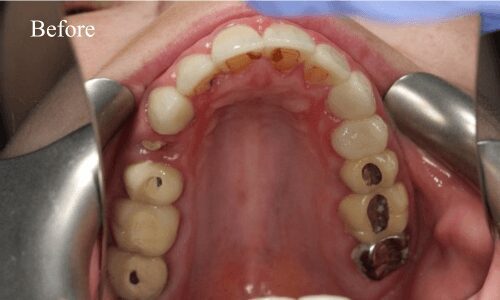

Full Mouth Rehabilitation

Full mouth rehabilitation or FMR is a restorative dental procedure which involves replacing all the teeth in the upper and lower jaws.This is a comprehensive treatment that combines general, cosmetic and restorative dentistry. This means you may have to get dental crowns, implants and whitening done at the same time to bring back the original strength, functionality, and aesthetic appeal of your teeth.